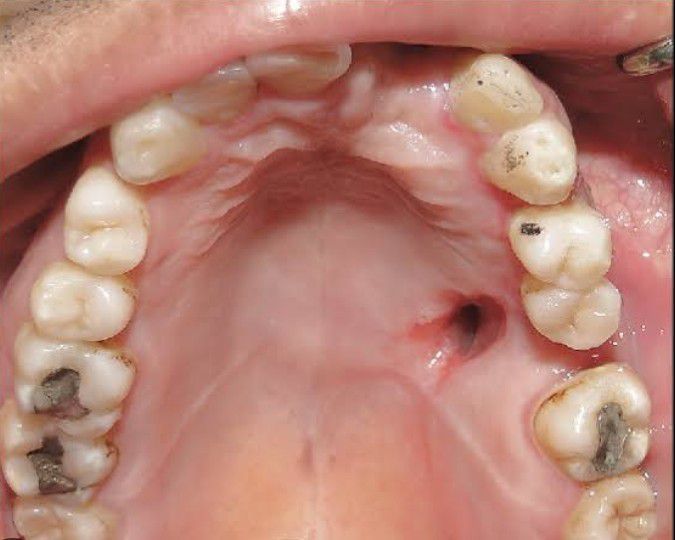

An oro-antral fistula (OAF) is an epithelialized pathological unnatural communication between oral cavity and maxillary sinus. It develops when the oro-antral communication fails to close spontaneously, remains patent and gets epithelialized.There is migration of oral epithelium into the defect.